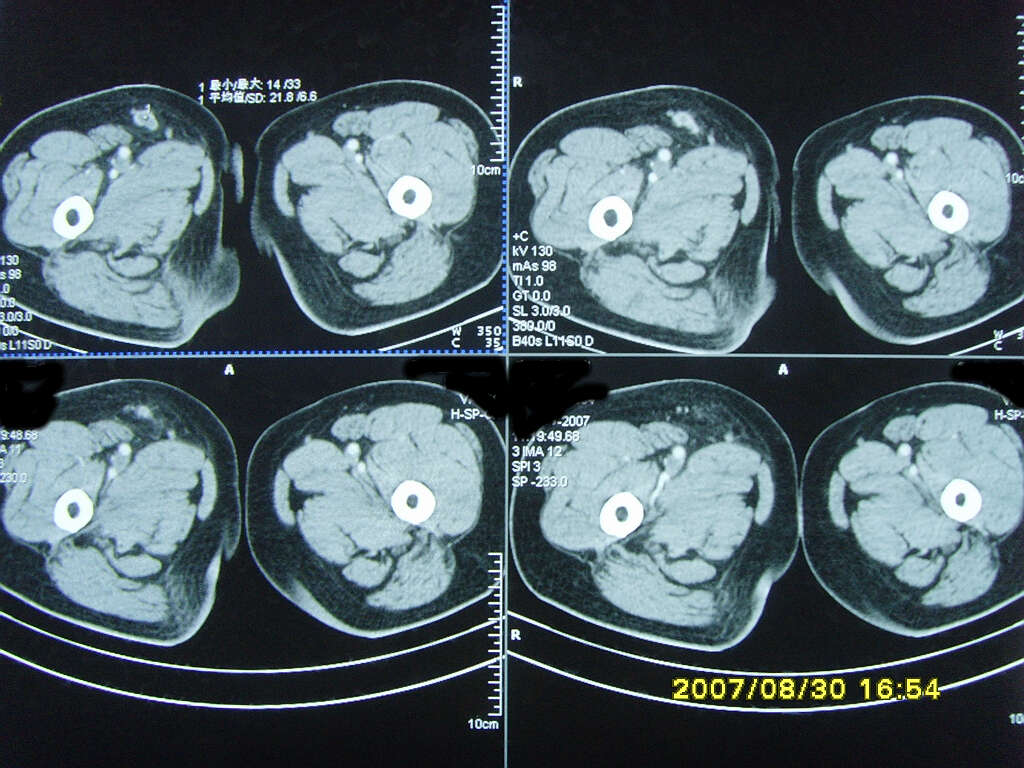

以下是引用zjzjr在2007-9-11 22:21:00的发言:[br]右侧股骨上段前部皮下可见不椭圆形软组织密度影,增强呈环形强化,周围皮下脂肪混浊,考虑感染性病变,不知临床症状如何.